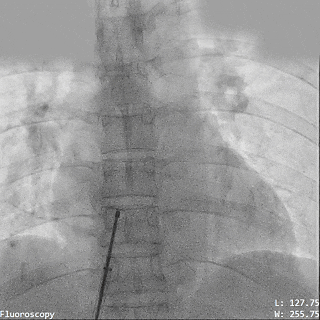

释放氧化膜封堵器左右盘面

牵拉试验封堵器稳定

释放封堵器

封堵器稳固夹持